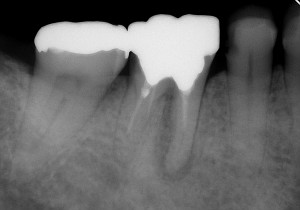

初診時は、時々歯肉から膿が出てきたり、鈍痛を感じることがあったとのこと。レントゲン写真を見ると確かに病気が出来ている影が・・・。さらに、この影の形を見るともしかしたら歯の根が割れているかもしれない。そうなると抜歯に移行しなければなくなる可能性もあることなど病気が治る喜びだけでなく、リスクや起こりうる可能性についても細かく説明させていただいた後に治療を開始しました。

↑初診時